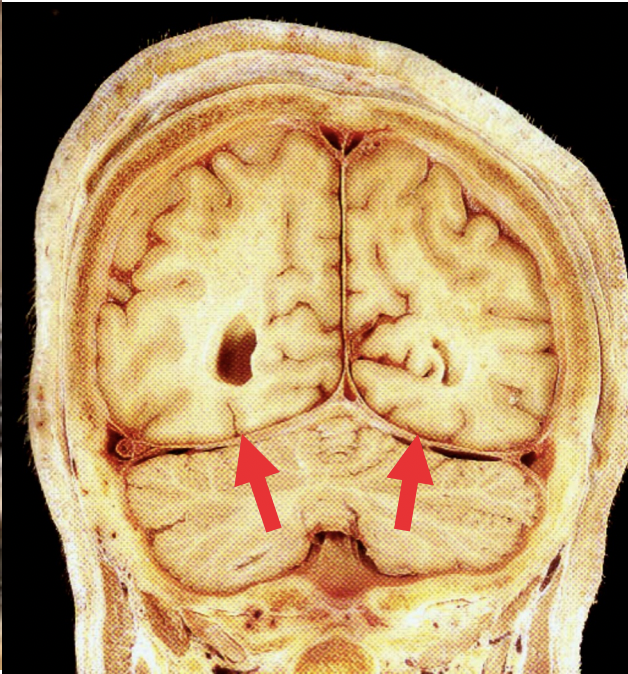

What are the names for the different combinations of the basal ganglia?

What is the anatomy of the basal ganglia

Model of caudate nucleus, thalamus and lentiform nucleus

Coronal section showing basal ganglia component

Structures here

A = Body of caudate nucleus B = Putamen of lentiform nucleus C = Hippocampus D = Parahippocampal gyrus

List the structures present here

A = Anterior horn of lateral ventricle B = Corpus callosum C = Insular cortex D = Globus pallidus E = Pineal gland

What are the structures labelled here?

A = Interpeduncular fossa B = 3rd ventricle C = Hippocampus D = Anterior horn of lateral ventricle E = Septum pellucidum